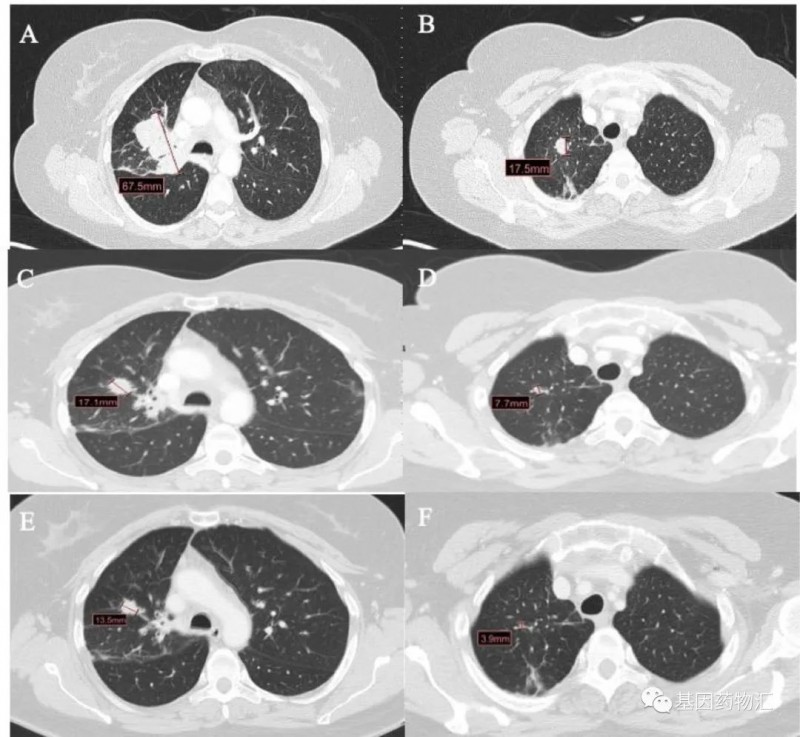

此后患者接受了Mobocertinib(TAK-788)的临床试验,达到了临床缓解,症状显著改善。至结果发布时,患者的疗效已经持续了超过8个月。